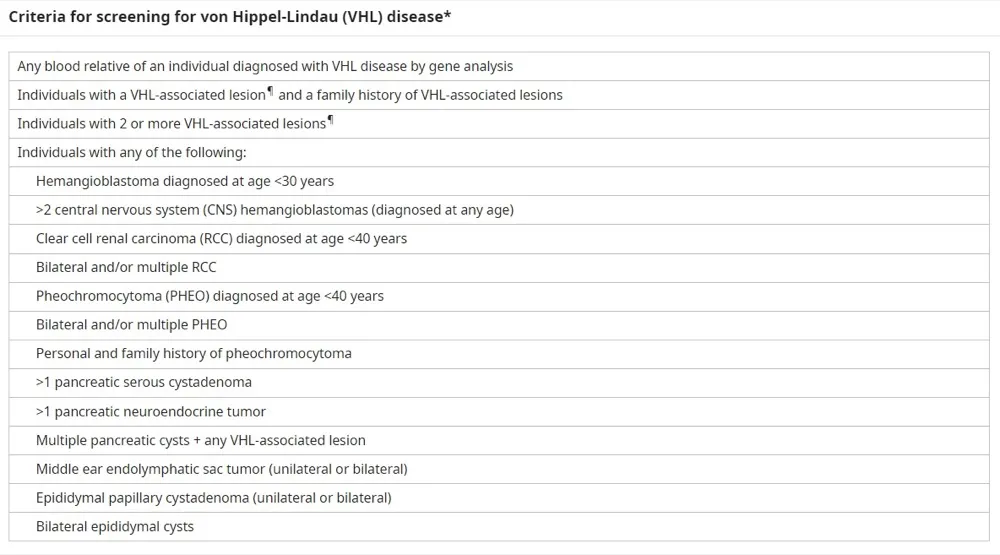

Quando suspeitar de um paciente com Doença de Von-Hippel Lindau?

* Diagnóstico carcinoma de células renais claras (CCR) com idade <40 anos

* CCR múltiplos e/ou bilaterais

* Feocromocitoma diagnosticado com idade <40 anos

* Feocromocitoma múltiplos e bilaterais

* História familiar ou pessoal de feocromocitoma

Confere essa tabela do UpToDate com os critéricos diagnósticos: